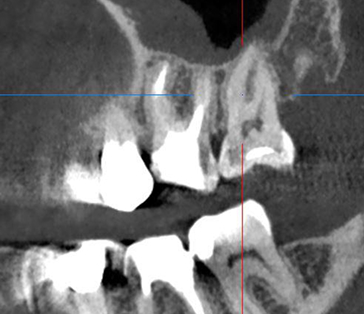

Сохранение зуба при наличии кисты, проростающей в гайморову пазуху

Проблема: У пациента боли в проекции гайморовой пазухи, заложенность носа, боли при пережевывании пищи.

Лечение: Проведено эндодонтическое перелечивание зуба под микроскопом: удалены ранее внесённые материалы, выполнена тщательная механическая и медикаментозная обработка корневых каналов с учётом их анатомии. Особое внимание уделено устранению инфекционного очага (кисты), связанного с воспалением в области гайморовой пазухи. После этого каналы герметично запломбированы, а коронковая часть зуба временно восстановлена для дальнейшего покрытия зуба коронкой.

Результат: После проведённого эндодонтического лечения болевые ощущения при жевании устранены, дискомфорт и давление в области гайморовой пазухи исчезли, восстановилось нормальное носовое дыхание. Зуб сохранён, его функция восстановлена. После фиксации коронки полностью восстановлены анатомическая форма и жевательная эффективность, нагрузка распределяется корректно.